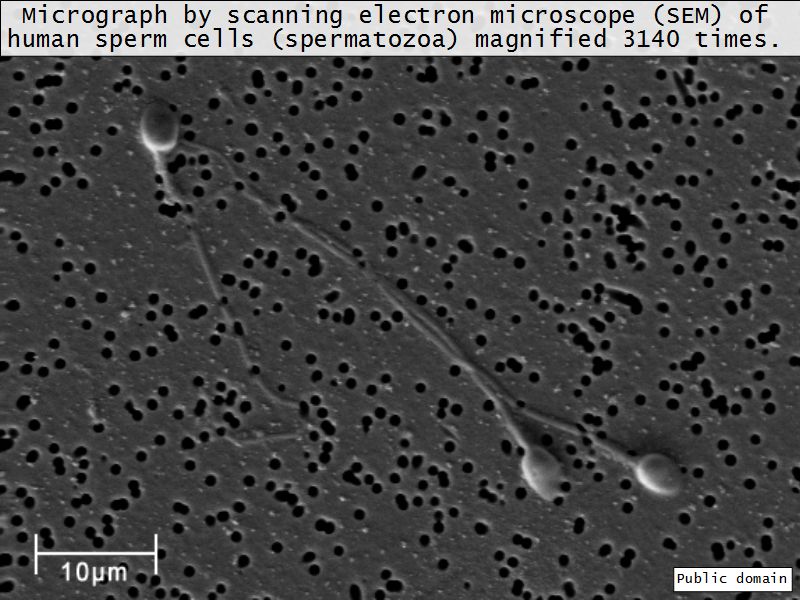

Spermatozoa

- Head

- Contains nucleus

- Dense chromatin

- Acrosomal cap anterior over nucleus

- Midpiece

- Mitochondrial sheath

- Small amount cytoplasm

- ATP for flagellar motility

- Tail

- Principle piece

- End piece

- Microtubuli for movement